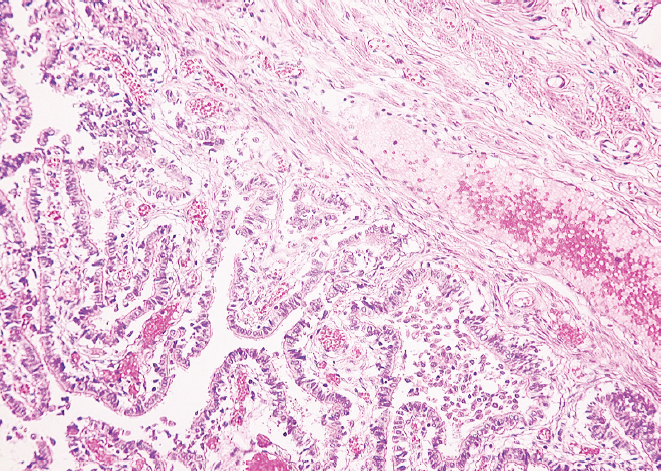

Гистологическое исследование препаратов показало, что в молодом возрасте слизистая оболочка перешейка и воронки маточных труб образует множественные продольные складки. Она представлена однослойным столбчатым эпителием и собственной пластинкой, которая образована рыхлой соединительной тканью. По ходу маточной трубы реснитчатые и секреторные эпителиоциты (экзокриноциты) располагаются неравномерно — реснитчатые преобладают в воронке маточной трубы, а секреторные — в области ее перешейка. Мышечная оболочка состоит из циркулярного и продольного слоев (рис. 1, 2).

Рис. 1. Фрагмент перешейка маточной трубы женщины в возрасте 25 лет. Окраска гематоксилином и эозином, увел. ×10

Рис. 2. Фрагмент воронки маточной трубы женщины в возрасте 25 лет. Окраска гематоксилином и эозином, увел. ×10